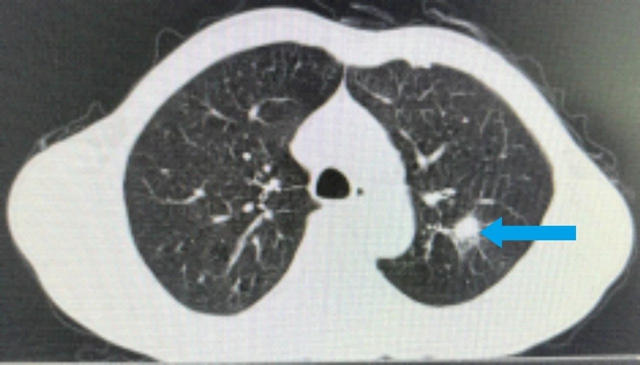

经积极治疗后,李大叔颈部包块基本消失,肺部病灶明显缩小,尤其是放疗期间李大叔头颈部放射性皮炎、放射性口咽炎轻微,生存质量高。

治疗3月后,李大叔复查胸部CT与上次比较,肺部结节缩小,大小约1.6×1.3cm²;复查鼻咽部MRI提示:鼻咽部病灶明显缩小,右侧咽旁间隙肿大淋巴结未见显示,颈部双侧淋巴结数量减少、体积缩小。